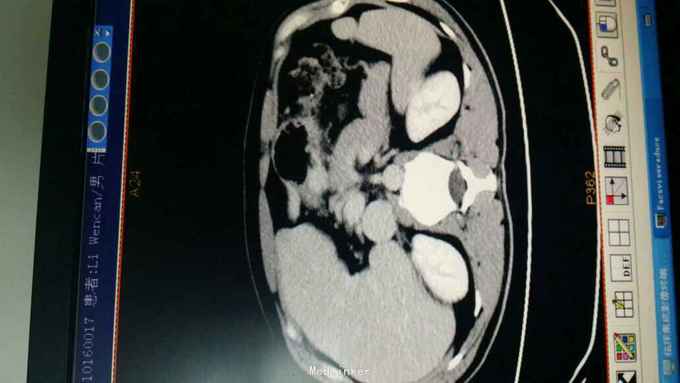

查体:T:36.8 ℃ P 85次/分 R:22 次/分 BP 119/79 mmHg 皮肤、巩膜无黄染,心、肺听诊无异常。腹部平坦,未见胃肠型及胃肠蠕动波,无腹壁静脉怒张,腹式呼吸活动不受限,腹肌柔软,全腹无压痛及反跳痛,肝区无压痛,肝浊音界位置正常,肝脾未触及,Murphy征(-),移动性浊音(-),双肾区无压痛及叩痛,肠鸣音正常,未闻及血管杂音。 辅助检查:1.血常规:WBC 7.9x109 /L,HGB 133 g/L,N 68.8%; 2.肝功能:TBIL 13.2μmol/L,DBIL 4.4μmol/L,TP 71.7g/L,ALB 44.3g/L,ALT 16U/L,AST 19U/L,GGT 15U/L,GLU 5.03mmol/L; 3.肿瘤标记物:CA199:38.64 U/ml,AFP、CEA、TPSA 未见异常。 4.胃镜+病理:胃体后壁溃疡,3.5cm×4cm,病理:(胃体)中分化腺癌,HP-。 5.全腹CT:胃体近胃窦处后壁局部组织不规则增厚。肝胆胰脾肾未见异常;右肺下叶背段肺大泡。

诊断:胃癌 治疗:入院后行常规术前检查,术前准备完善后在气管内插管全麻下行腹腔镜胃癌根治术,术中探查肝脏及腹腔其它部位未见明显肿瘤转移。肿瘤位于胃体近胃窦处后壁,肿瘤侵出浆膜,与胰腺被膜少许粘连。腔镜下行远端胃大部切除术,清除胃周围淋巴结,于腔镜下行结肠前胃空肠端侧吻合(毕Ⅱ式吻合) 。手术顺利,术后恢复好,术后第4天拔除胃管,第5天进食流质饮食,术后1周出院。术后病理报告:胃中分化腺癌,覃伞型,3.5cm×4cm,侵润胃壁全层,近、远两切缘未见癌累及。淋巴结见转移癌(第一组0/0,第八组0/2,第十一组0/0,胃小弯侧12/14,胃大弯侧8/9,大网膜0/0)。免疫组化结果尚未回报,待免疫组化结果回报后再行综合治疗。